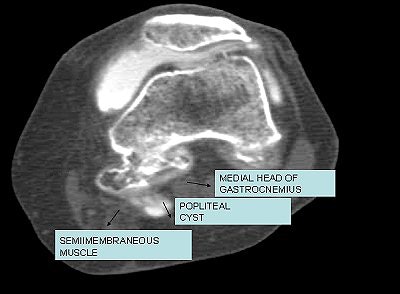

![]() |

| Iodinated contrast-enhanced (8 cc delivered to the knee joint) CT arthrogram (Sytec SRi, GE Healthcare). One-millimeter axial scans (kVp 120; mAs 80) of the joint were performed. There is extravasation of contrast in the synovial cyst between medial gastrocnemius and semimembranosus tendon. Image courtesy of Dr. Shamim Malk. |